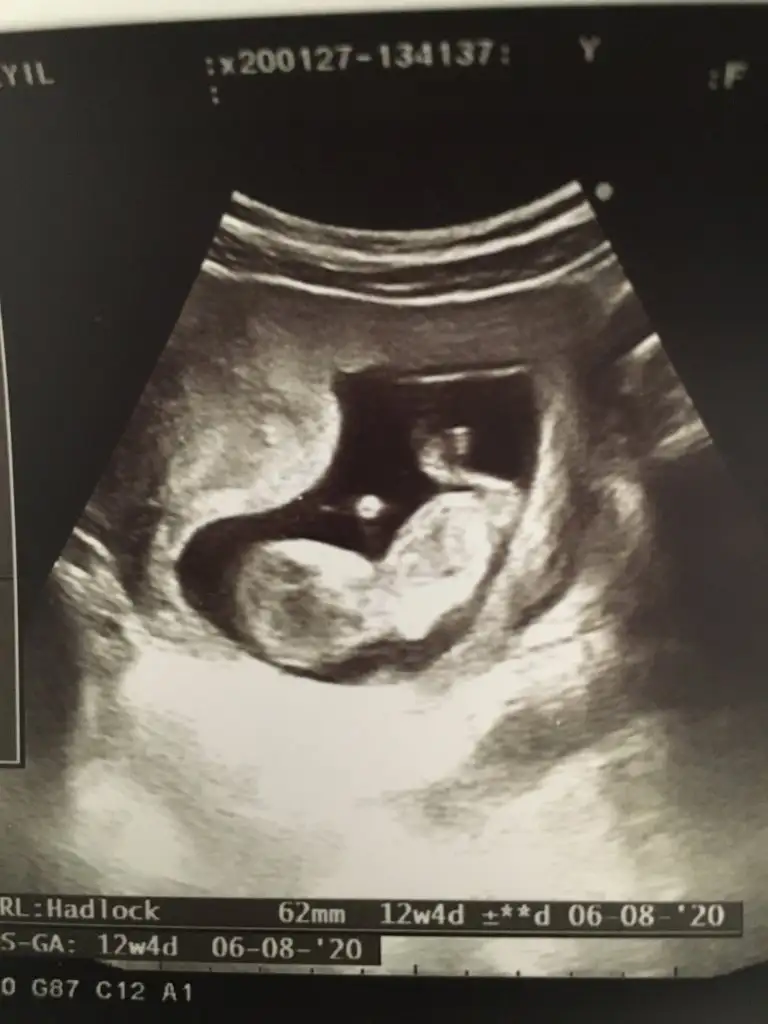

İkra meyra 12 haftalık ken tekrar foto atın demiştiniz burda 12+5 sizce cinsiyet ne ?

Eklentiler

• EDF88188-D37F-4A20-999C-B32BE1D02EF0.webp

EDF88188-D37F-4A20-999C-B32BE1D02EF0.webp

37 KB · Görüntüleme: 56